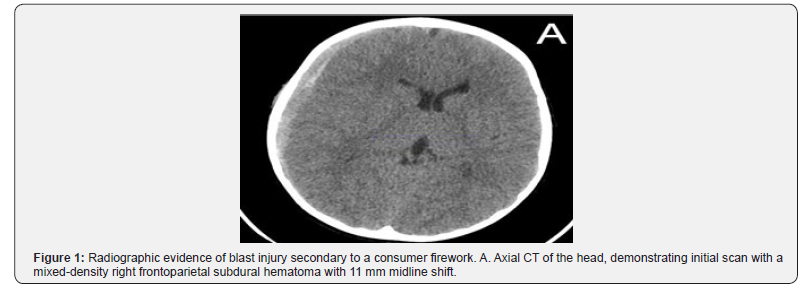

On initial presentation, the patient had a Glasgow Coma Score (GCS) of 14 with confusion regarding the year and his location, in addition to left lower extremity weakness. He had a 5 cm burn over his right temple with surrounding facial edema. Computed Tomography (CT) of the head demonstrated a 9mm mixed-density right convexity subdural hematoma with 11 mm of midline shift (Figure 1). No skull fracture was identified(Figure 2). While in the trauma bay, he had a steady decline in consciousness. Due to the large subdural seen on imaging and concordant worsening exam findings, the decision was made to proceed with surgical intervention for evacuation of the hematoma (Figure 3).